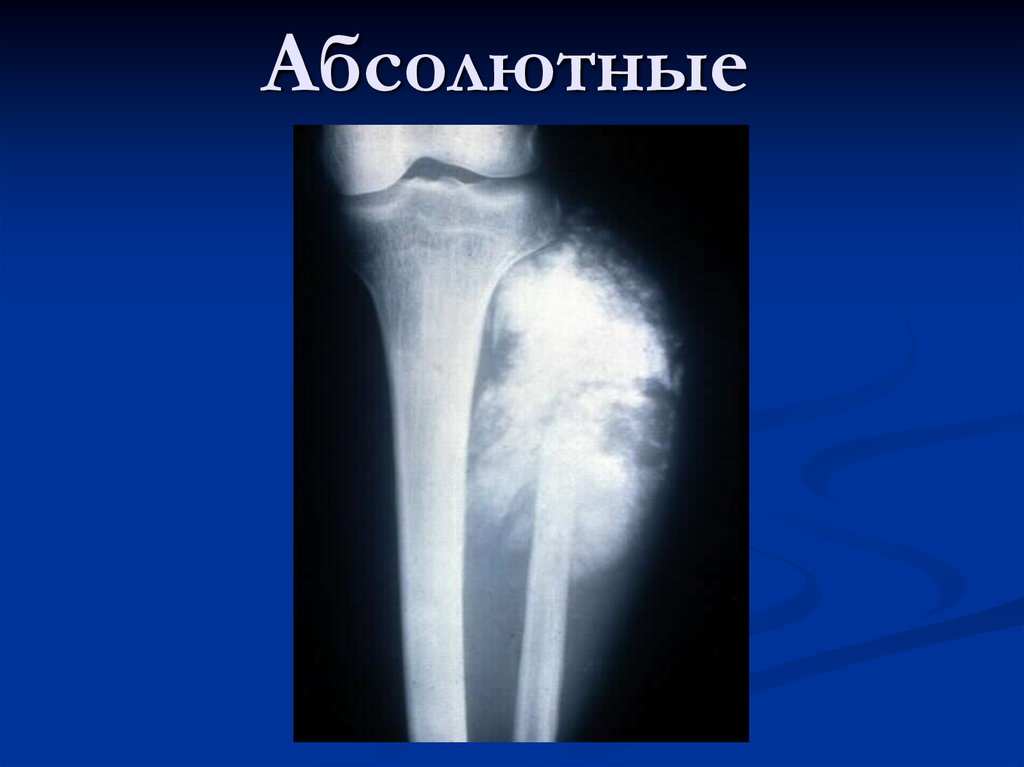

Рентгеновские снимки саркомы плечевого сустава